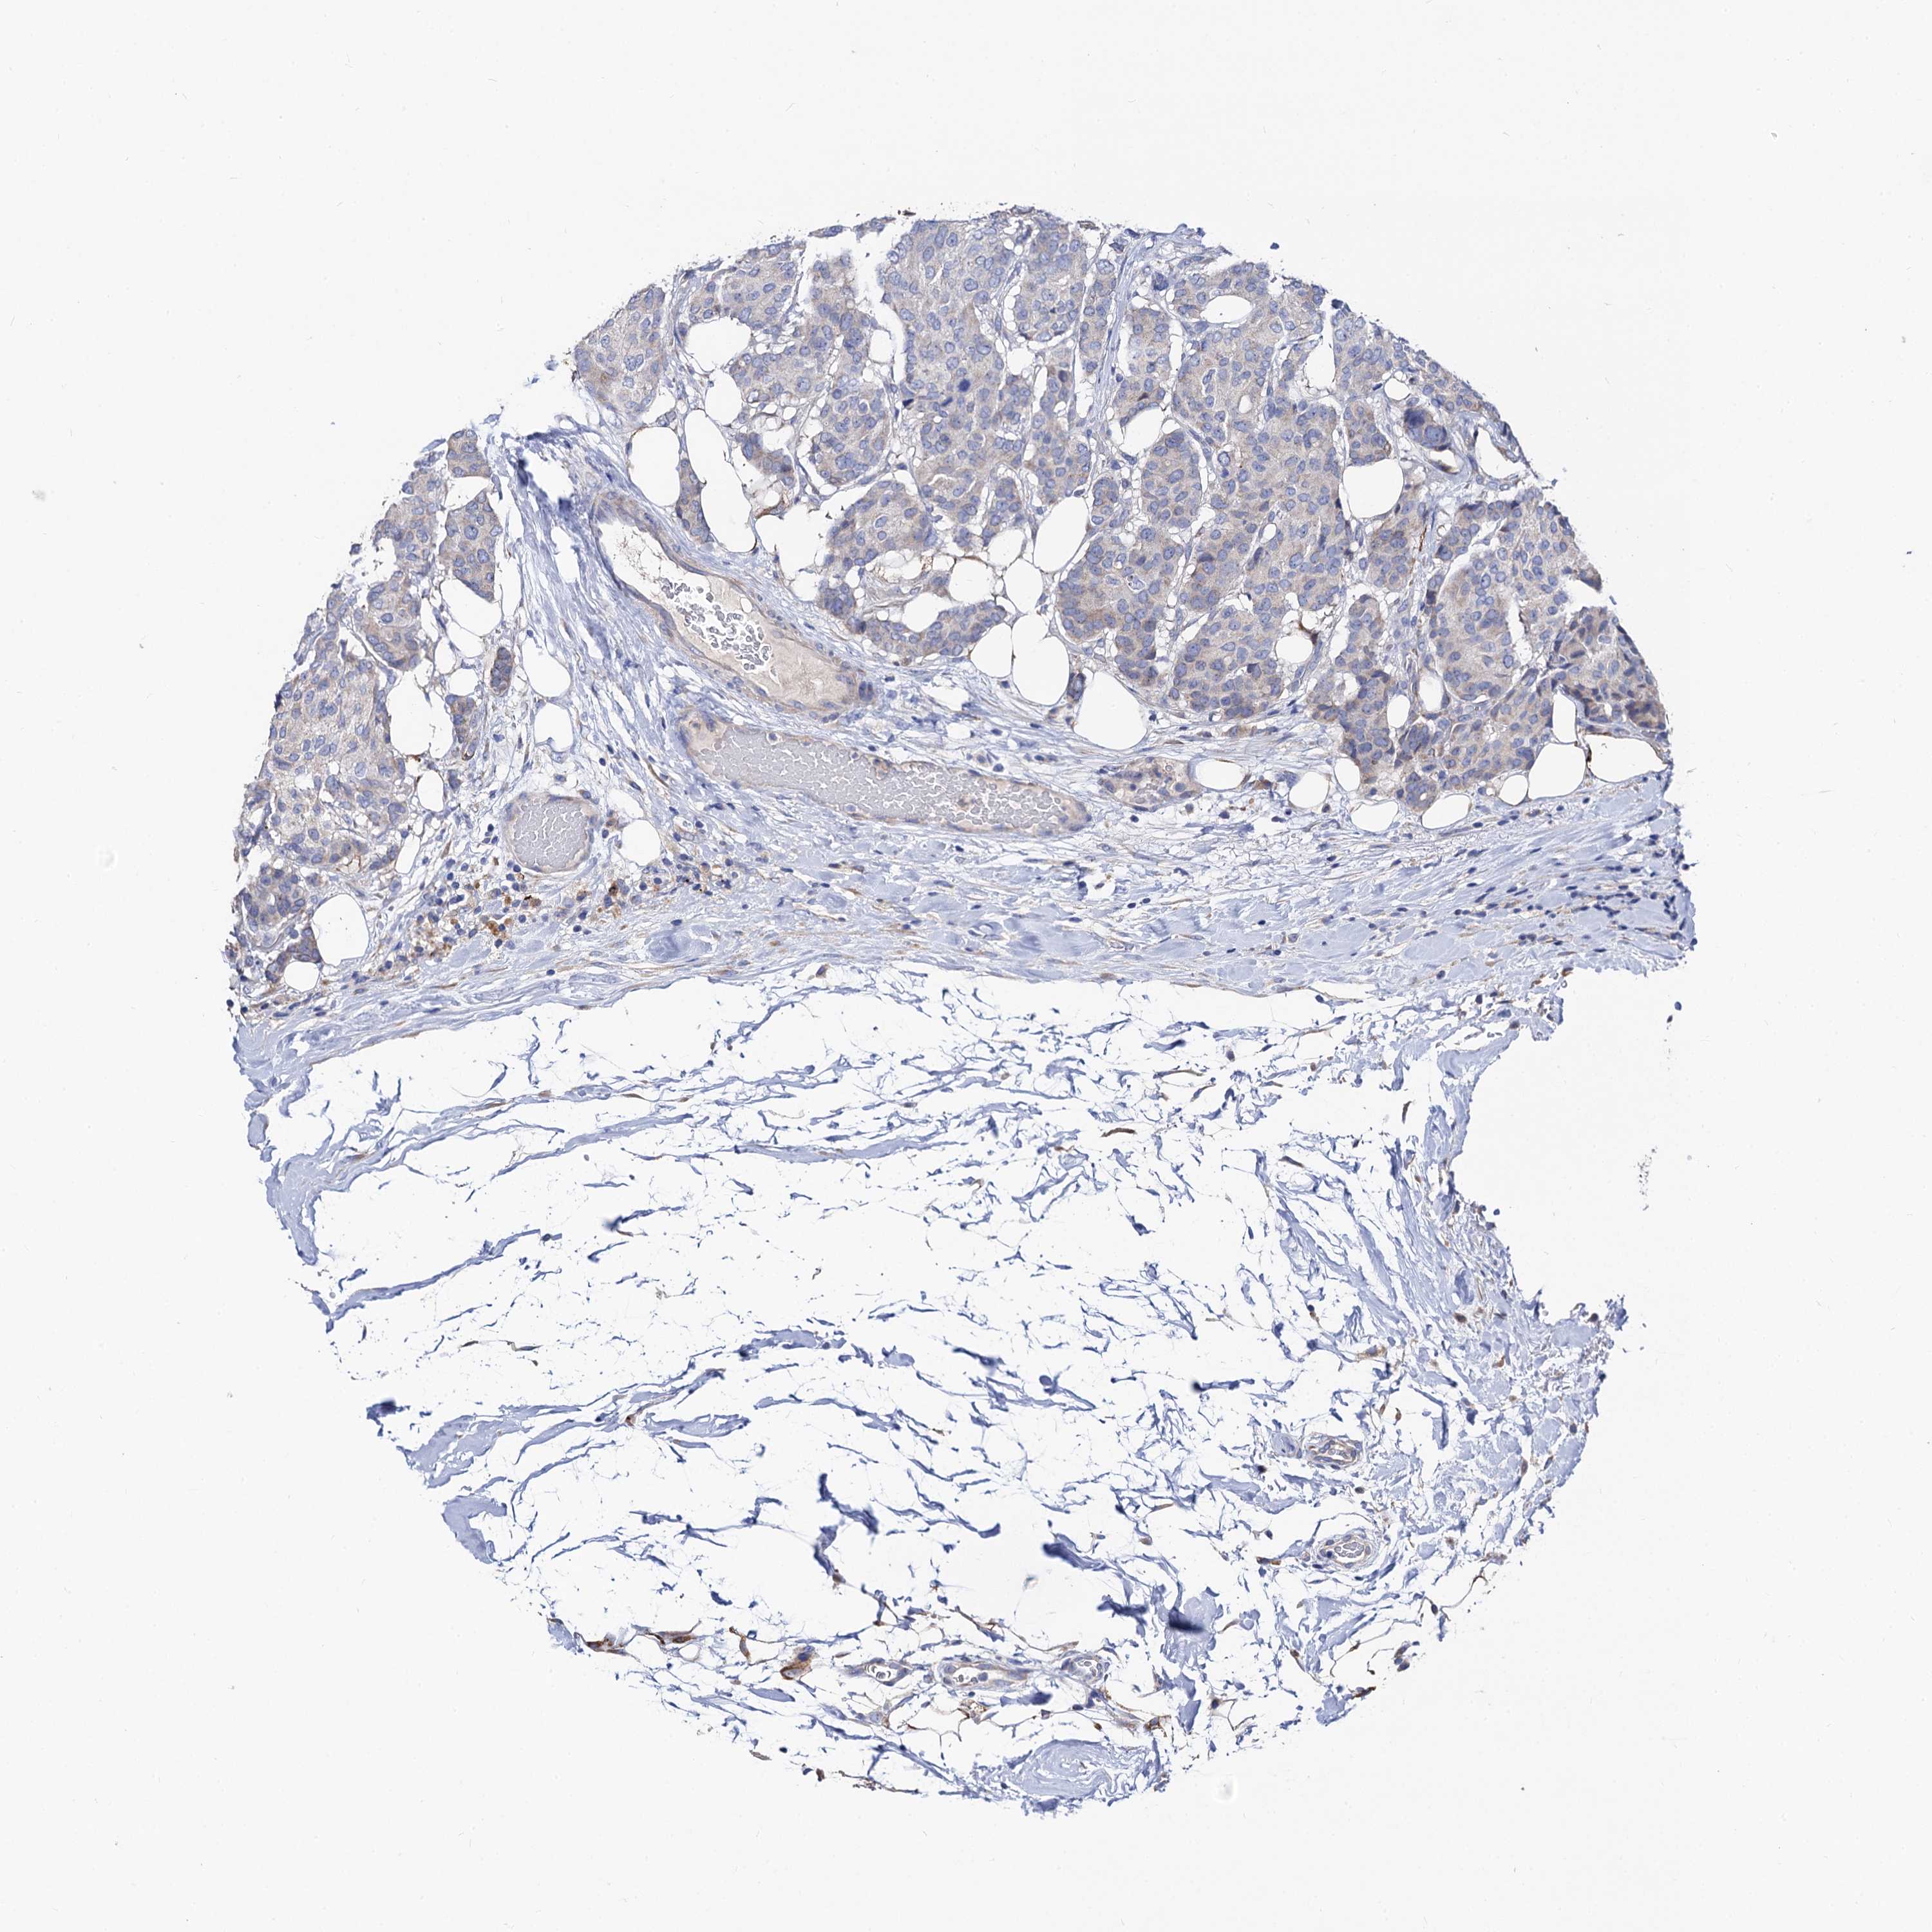

CANCER BREAST CANCER Show tissue menu

BRCA TCGA BRCA VALIDATION PROTEIN EXPRESSION